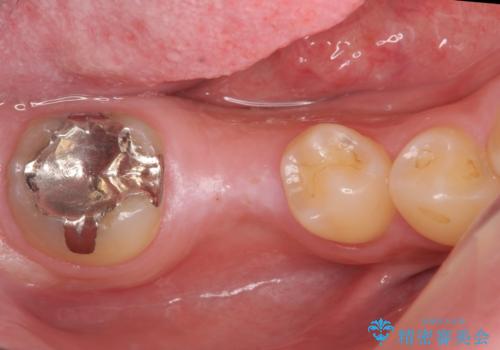

- 45万円(税別) 内訳:ストローマンインプラント(1本)20万円、ジルコニアクラウン10万円、シリンダーTeC 2万円 ジルコニアカスタムアバットメント10万円 ホワイトニング(エクセレント)3万円費用は治療当時の料金となります

ブリッジにすることも可能でしたが、両側の歯が天然歯であること、また、事前に矯正で噛み合わせを整え、幅も確保していたこと、CTにより骨の厚みがある程度あったことを踏まえ、インプラントも可能であるとお話しし、選んでいただきました。